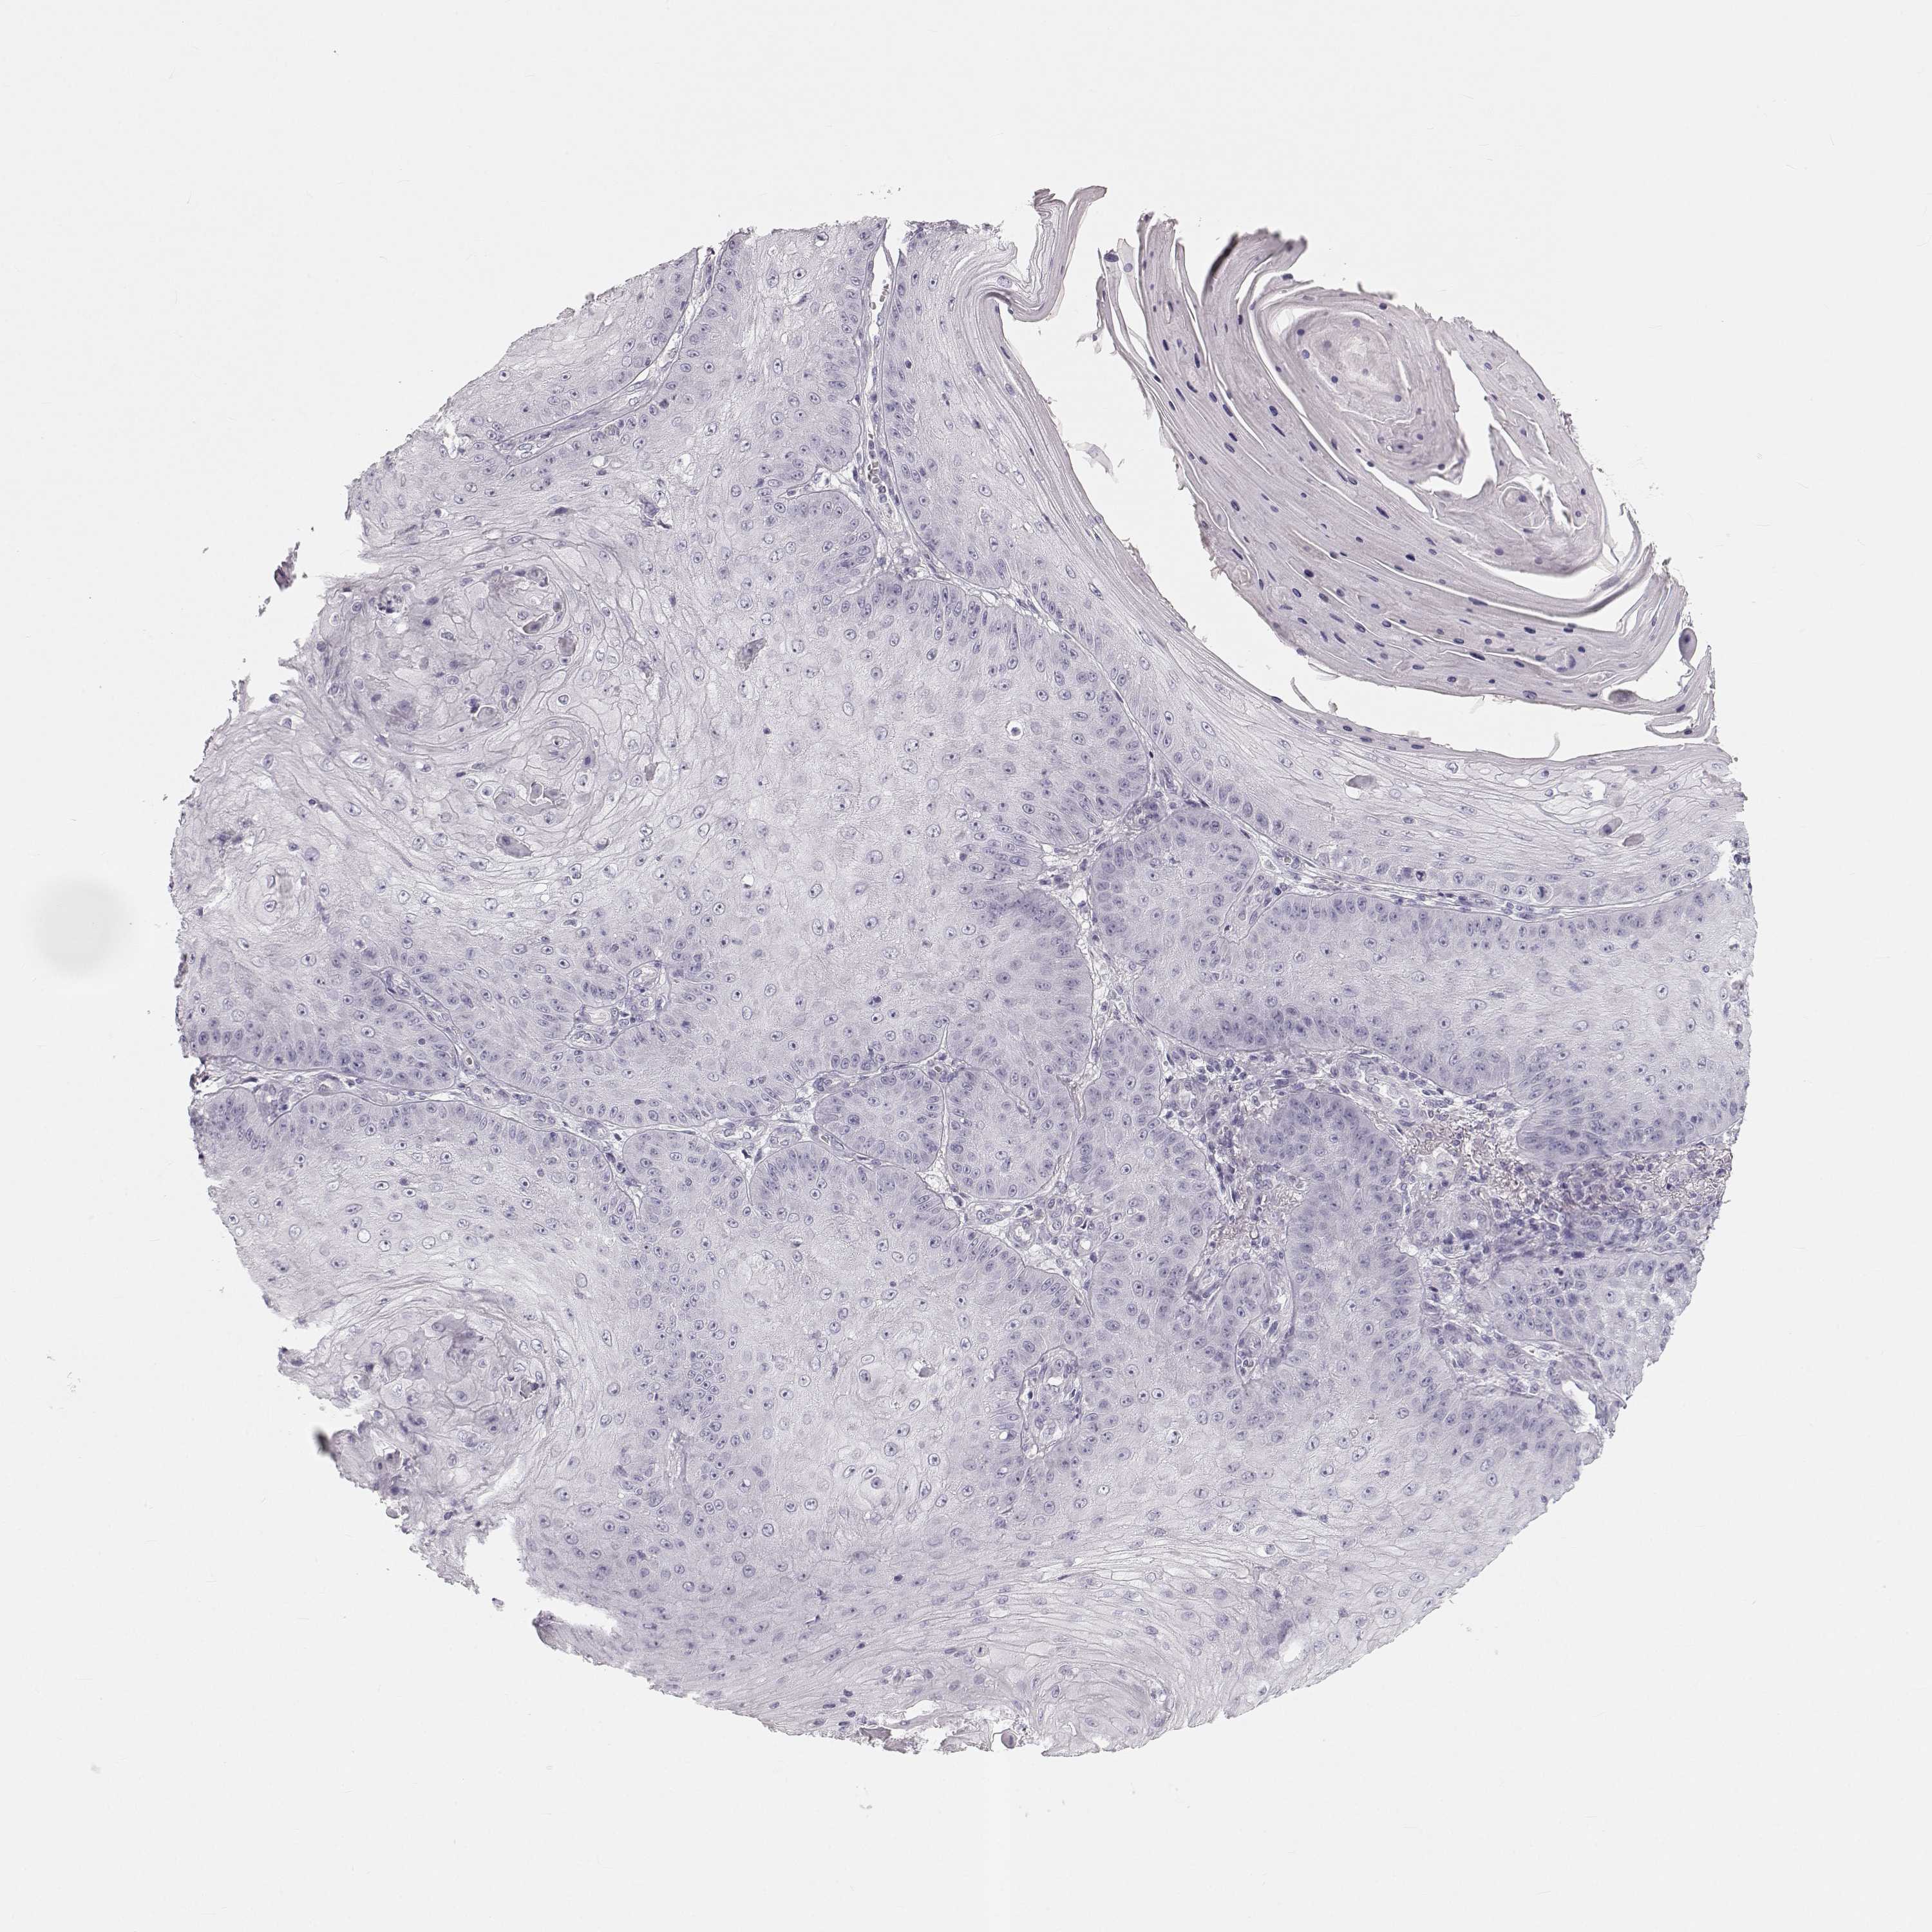

Basal cell and squamous cell cancer

SKIN CANCER - Protein expressioni

A mouse-over function shows sample information and annotation data. Click on an image to view it in a full screen mode. Samples can be filtered based on level of antibody staining by selecting one or several of the following categories: high, medium, low and not detected. The assay and annotation is described here.

Antibody stainingi

Antibody staining in the annotated cell types in the current human tissue is reported as not detected, low, medium, or high, based on conventional immunohistochemistry profiling in selected tissues. This score is based on the combination of the staining intensity and fraction of stained cells.

Each image is clickable and will lead to virtual microscopy that enables deeper exploration of all samples and also displays staining intensity scores, fraction scores and subcellular localization as well as patient and tissue information for each sample.

Antibody HPA052271

Antibody HPA059602

Staining

High

Medium

Low

Not detected

Intensity

Strong

Moderate

Weak

Negative

Quantity

>75%

75%-25%

<25%

None

Location

Nuclear

Cytoplasmic/membranous

Cytoplasmic/membranous,nuclear

Basal cell carcinoma

Squamous cell carcinoma, NOS